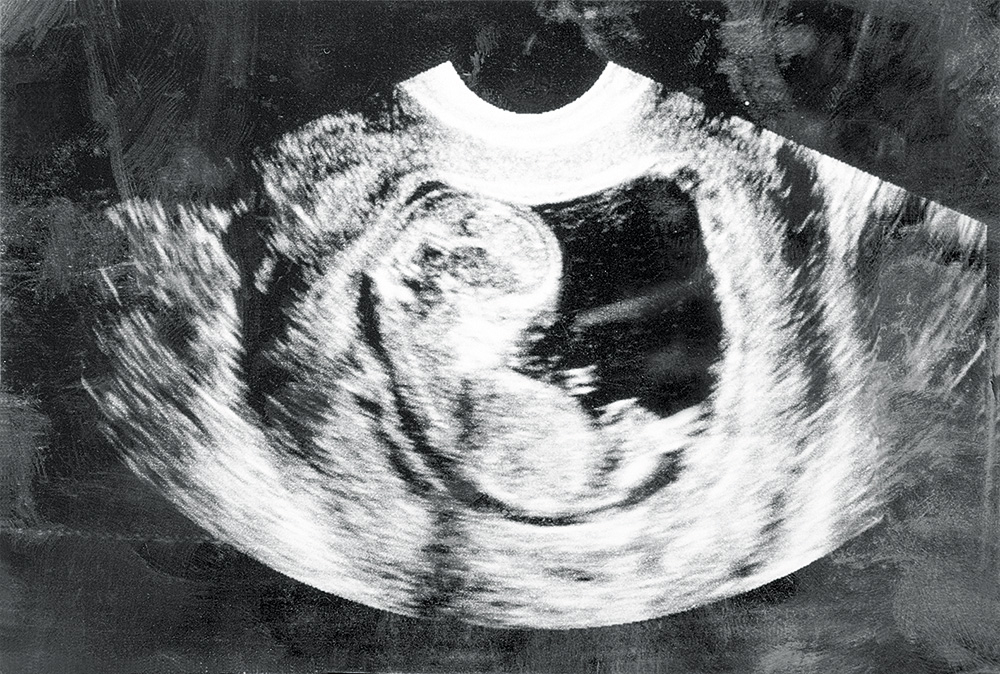

Embrija attīstības process joprojām ir viena no lielākajām, vēl neatminētajām mīklām un vienlaikus arī neviltotas sajūsmas objekts. Jautājumu ir daudz, piemēram: kā šūnas savācas kopā, lai spētu izveidot sarežģītas struktūras, kādas ir orgāni, locekļi un viss tamlīdzīgais?

Lai arī atbilžu meklēšana šeit ir ļoti sarežģīta, tomēr jau tagad pētnieki guvuši gluži vērā ņemamus panākumus nolūkā izprast vienu no svarīgākajām embrionālās attīstības stadijām – gastrulāciju. Tas ir process, kura gaitā embrija šūnas no vienlīmeņa struktūrām pārtop daudzdimensionālās struktūrās ar ķermeņa galveno asi. Cilvēkam tas parasti notiek 14 dienas pēc ieņemšanas, taču embrija pētīšana šādā stadijā nav iespējama, un saistībā ar to amerikāņu un britu pētnieku apvienotā komanda izpētīja vistu embriju, kam piemīt ļoti daudz kopīga ar šajā stadijā esošajiem cilvēku embrijiem.